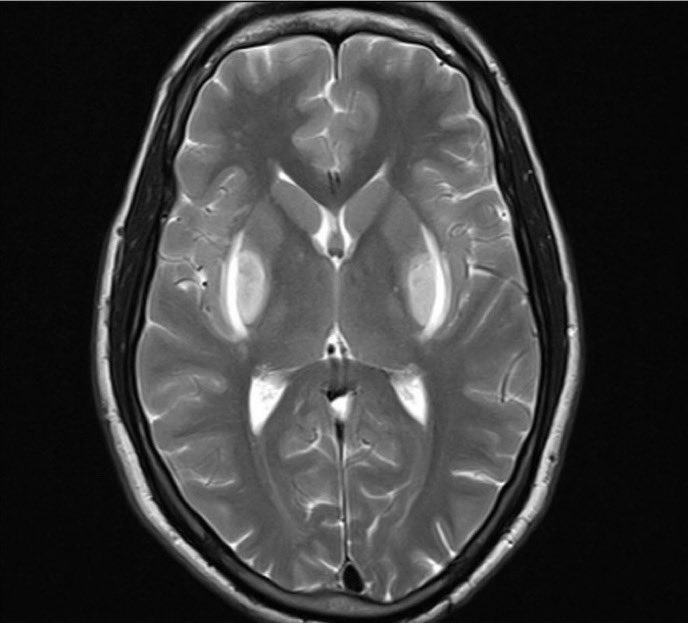

@alhasandr1 @MattersoftheH14 @ED_Ultrasounder @doctor_roig @EM_RESUS @smithECGBlog @ECGfan @rob_buttner @EkgHacks @ecgrhythms @OnlyEcg1 @CardiacPA1 @ekgdx @TheEKGGuy @BrooksWalsh Terminal R in AVR with RS ratio greater than 0.7…wide complex, could it possibly be due to TCA OD?